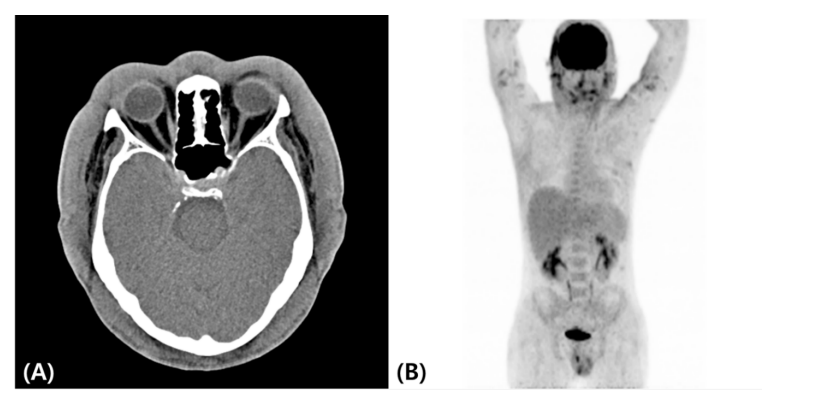

A computed tomography (CT) scan from the craniofacial area to the pelvis showed splenomegaly and diffuse soft tissue swelling of the head, face, neck, and trunk (Figure 3A). Positron emission tomography CT revealed metabolic uptake along the face, both upper and lower extremities, and the cutaneous area of the trunk (Figure 3B). A subsequent study revealed the presence of HLH, including bone marrow hemophagocytosis, cytopenia, hypertriglyceridemia, hyperferritinemia, elevated soluble interleukin 2 receptor alpha levels, and low natural killer cell activity. Other laboratory studies showed minimal IgG monoclonal gammopathy and negative blood Epstein-Barr virus test results.

Figure 3: Computed tomography image showing diffuse craniofacial soft tissue swelling; (A) Positron emission tomography–computed tomography image showing mild to moderate metabolic uptake along the cutaneous areas of the face, both upper and lower extremities, and the trunk (B).